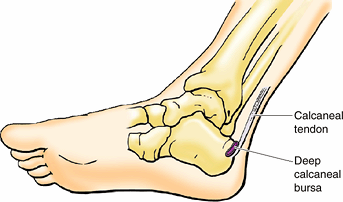

Leg (L. crus) or leg region (L. regio cruris).

Although laypersons refer incorrectly to the entire lower limb as “the

leg,” the leg is the part that lies between the knee and the rounded

medial and lateral prominences (malleoli) that flank the ankle joint. The leg contains the tibia (shin bone) and fibula (L. buckle) and connects the knee and foot. The calf (L. sura) of the leg is the posterior prominence caused by the triceps surae muscle, from which the calcaneal (Achilles) tendon extends to reach the heel. -